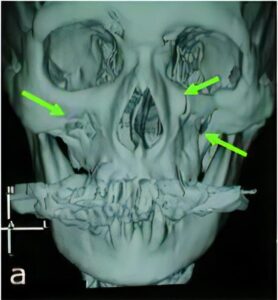

外傷

連携病院である沼田脳神経外科循環器科病院は、救急指定病院ということもあり、当院でも顎口腔領域の骨折や裂傷、歯牙破折や脱臼などの患者さんの治療も行っております。

奇形・変形症

顎変形症 (受け口などの上下の顎のバランスが悪い方や顎の変形で正しく噛み合わない) の方に関しても矯正治療と手術(顎矯正手術)が必要になる場合があります。群馬大学や新潟大学医歯学総合病院顎顔面外科口腔外科診療室にご紹介しております。